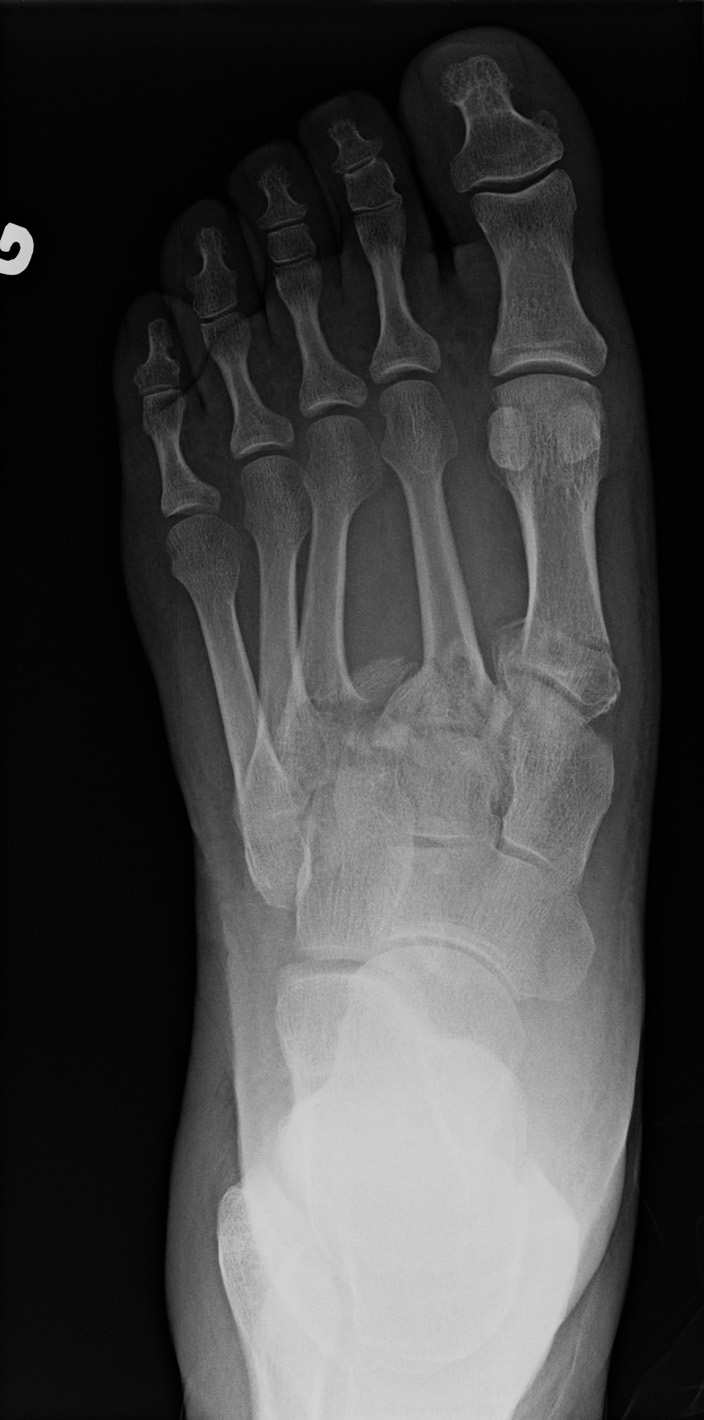

54-year-old male:

High velocity car crash.

Lisfranc fracture

First, note the base fractures of the 1st and 2nd metatarsal bones, minimally displaced, yet angulated in valgus. Second, note the three lateral metatarsal bones laterally displaced and with a varus angulation; the 3rd one is fractured and the 4th and 5th ones are dislocated. Thus, this is a Lisfranc fracture-dislocation of the divergent type. However, this is actually an atypical Lisfranc injury, for the 1st and 2nd metatarsals are both displaced medially and the 3rd, 4th and 5th are displaced laterally. In a classic Lisfranc injury, only the 1st metatarsal deviates medially, while the 2nd, 3rd, 4th and 5th are all displaced laterally.

2nd metatarsal alignment

On the anteroposterior view, the intermediate cuneiform's medial border is partially aligned with the second metatarsal bone's medial border.

Bony fragment

Multiple bony fragments of the 3rd metatarsal base can be seen between the 2nd and 3rd metatarsal bones.

Anteroposterior